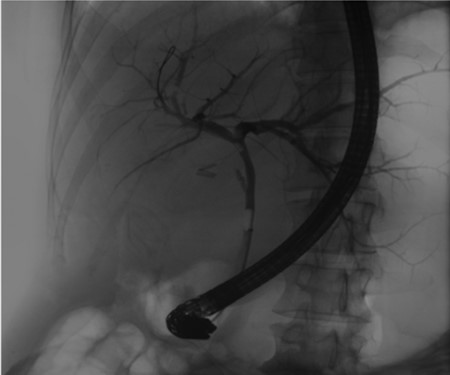

Pre-operative ERCP demonstrating compression of the common hepatic duct.

A 35-year-old female with a medical history significant for acute biliary pancreatitis status post laparoscopic cholecystectomy, presented to the surgery clinic as a new consult for a large cystic liver mass with increasing abdominal pain for 2 weeks. Patient reported suffering from severe pain in right chest, shoulder and diffuse abdominally that worsened with standing. Patient complained of inability to inspire due to pain and a 10-pound weight gain over 2 months. She confirmed decreased appetite especially with solids, nausea and emesis, alternating constipation and diarrhea, bruising, and pruritus at night. Computed tomography (CT) scan demonstrated a peripherally septated 10 x 7 cm cystic mass in the liver with intrahepatic biliary dilation (Fig. 1). The patient was referred for endoscopic retrograde cholangiopancreatography (ERCP) to establish preoperative biliary anatomy and was found to have moderate compression of the common hepatic duct managed with a right hepatic biliary endoprosthesis (Fig. 2); no obvious communication of the biliary tree with the cystic lesion was seen. Patient symptoms persisted despite optimizing with a protein-rich liquid diet; thus, the decision was made to proceed with the surgical plan for an open partial central hepatectomy. The patient was taken to the operative theater. After induction of general anesthetic, an upper midline incision was made. Inspection of the abdomen and liver showed no metastatic lesions grossly or with ultrasonographic imaging. The cyst was visible upon entry into the abdomen with no solid component to the mass in proximity to the cystic neoplasm. The second portion of the duodenum was adherent to the cyst with inflammatory adhesions and was quite boggy. A partial central hepatectomy was performed; a 3 mm biliary duct was found communicating to the cyst only with no drainage to the minimal liver parenchyma that was removed (Fig. 3). The cyst was resected en-bloc and was sent for permanent section (Fig. 4), which diagnosed the tumor as a low-grade mucinous cystic neoplasm measuring 8.5 × 7.2 × 6.4 cm. Microscopy revealed a smooth-walled, multiloculated cyst filled with a yellow-golden, semi-transparent and mucinous fluid (Fig. 5a–c). The cyst was lined by a mucinous epithelium with ovarian-type stroma. No high-grade dysplasia or malignancy was identified. The postoperative course was uneventful, and the patient was discharged on postoperative day 6. At the 4-week postoperative visit, the patient was healing well with some incisional soreness; patient was seen for removal of her biliary endoprosthesis, and ERCP found left sided intrahepatic duct biliary dilatation including a small biliary fistula from the left system (Fig. 6) with the appearance of torque on the extrahepatic biliary tree. A biliary endoprosthesis was left in place, and the patient returned for repeat ERCP 4 weeks later with resolution of all findings (Fig. 7). At present, patient remains alive with no signs of recurrence.